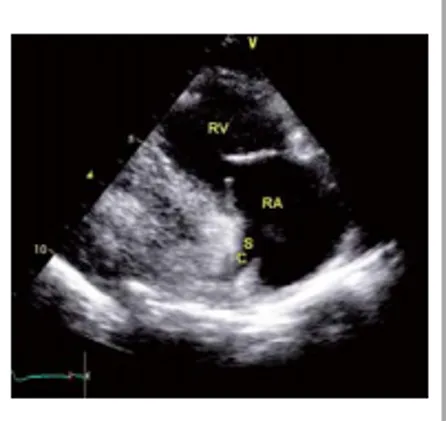

胸骨旁右心室流入道切面

探头位置:探头置于胸骨左缘3、4肋间,在左心室长轴切面基础上顺钟向调整探头15°—30°。

观察内容:右房、右室、三尖瓣前叶、后叶。